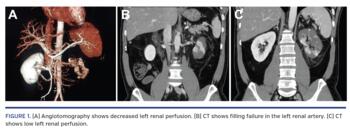

During hospitalization, echocardiogram (Figure 3) and Holter monitor were requested. Previous cardiac catheterization showed anterior descending artery with a discrete lesion and small diagonal branch with a severe lesion, and we opted for clinical treatment. Left ventriculography and echocardiogram revealed thrombus at the apex and preserved global function. Holter monitor showed absence of paroxysmal tachyarrhythmias.